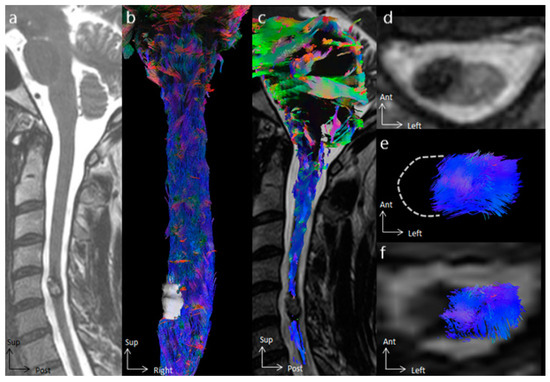

3.2. Tractography Rendering

4.2. The Added Value of Tractography